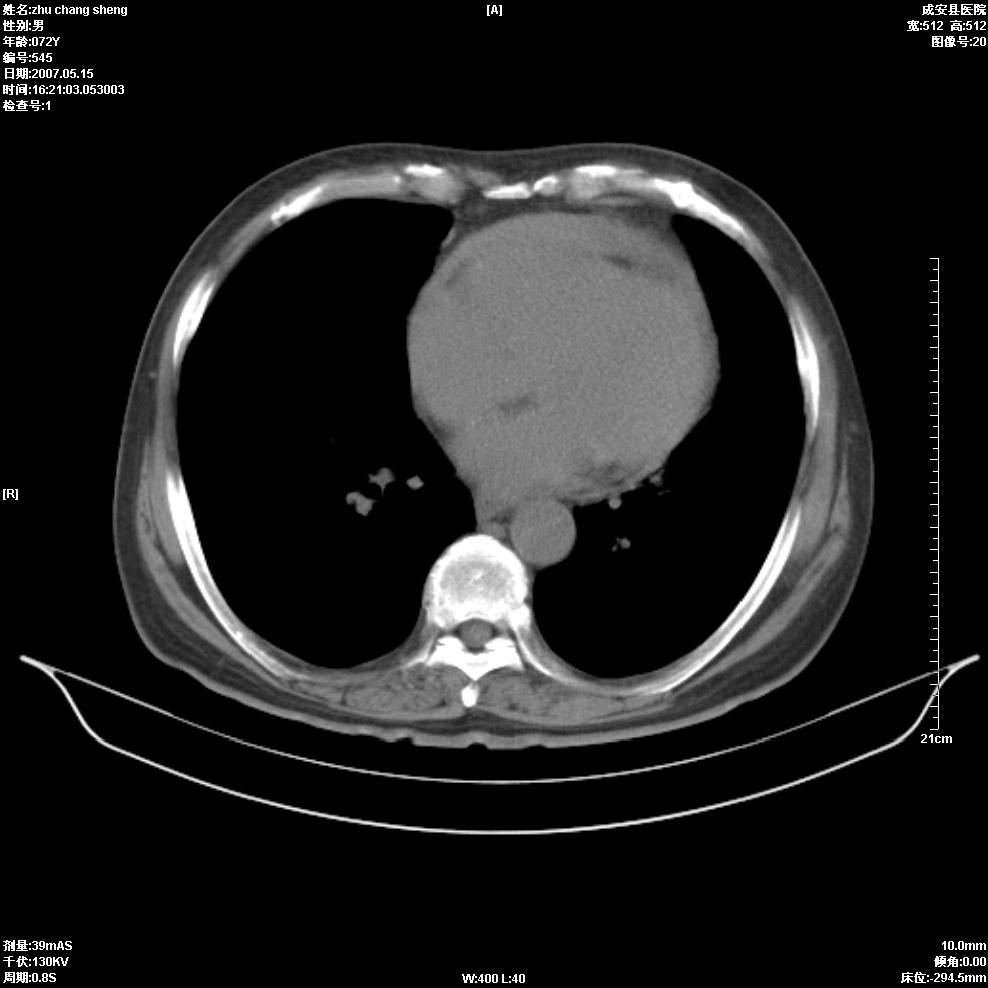

以下是引用医博云天在2007-5-15 19:10:00的发言:[br]心包积液,胸腔积液,心影增大,左心为主。

以下是引用zhangzhongshou在2007-5-15 20:21:00的发言:[br]心包积液可以肯定有,肿块显示不清,建议增强或mri检查。

以下是引用jinning在2007-5-15 21:06:00的发言:[br]心包积液可以肯定,建议增强或mri检查吧!

以下是引用拾荒者在2007-5-15 22:28:00的发言:[br]心包膜增厚,有少量积液,右室前壁示均匀软组织密度影,边界欠清,建议增强扫描或mri检查与室壁瘤鉴别。

以下是引用还珠格格在2007-5-19 9:50:00的发言:[br]病人与5月18日 做了核磁增强扫描 确诊为前上纵隔侵袭性胸腺瘤。